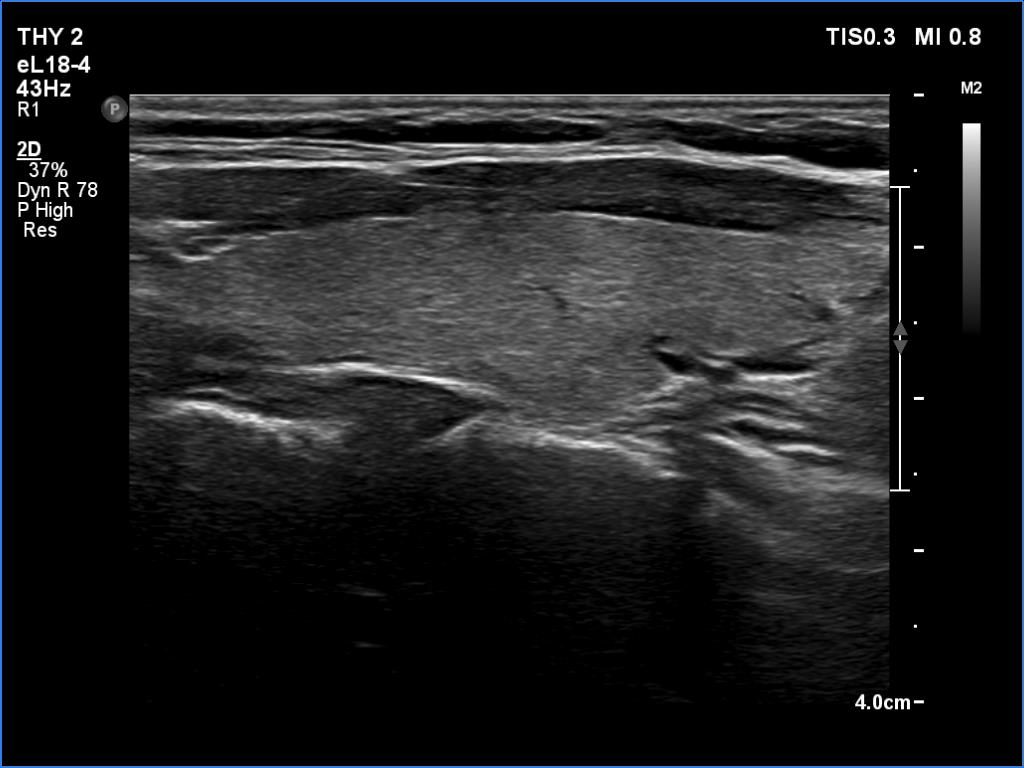

Initial examination (first row of images):

Clinical presentation: A 39-year-old woman was referred for evaluation of neck complaints lasting for more than a month. The patient had fever, neck pain. She has got two courses of antibiotics and non-steroid anti inflammatory drugs which had no effect.

Palpation: The right lobe was painful and hard while the left lobe was tender.

Laboratory examination: TSH 0.01 mIU/L, FT4 29.1 pM/L, FT3 7.45 pM/L, CRP 31.2 mg/L.

Ultrasonography: The thyroid presented with hypoechoic areas which had blurred borders. The echogenicity index was approximately 65% in the right and 20% in the left lobe. The thyroid was almost completely avascular.

Diagnosis: subacute, granulomatous de Quervain's thyroiditis.

Suggestion. Steroid therapy was suggested.